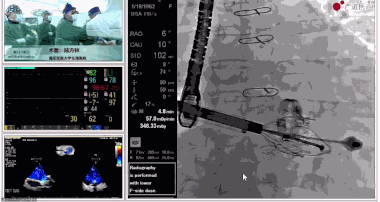

▲瓣膜植入過程

▲瓣膜植入后釋放的過程